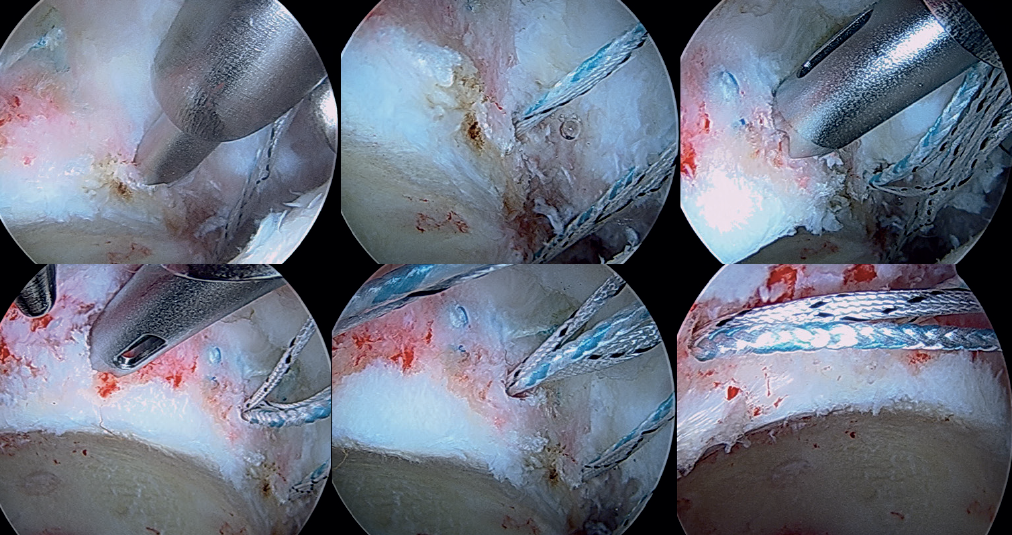

Insertion of the graft

Forceps are inserted from the posterior portal, taking care that they lie posterior to the last anchoring, and from the anterior modified portal we introduce the suture anchored to the anterior portion of the graft, likewise taking care that it lies anterior to the most anterior anchoring. Once within the joint, this suture is grasped with the forceps inserted from the posterior portal, and then traction is exerted posterior until it emerges from the posterolateral portal. Lastly, traction is continued to introduce the graft, making it emerge through the posterolateral portal. At this point, the anchoring preassembled in the graft is guided towards the pre-drilling made and is inserted, thereby fixing the most anterior portion of the graft in the case of using a knotless anchoring or extracting the suture and threading the tendon to then perform a knotted technique(Figure 12). After positioning and fixation of the most anterior portion of the graft, the filaments are passed around the graft in sequence, and are tightened little by little, maintaining traction from the posterolateral portal, and fixing and positioning the entire plasty from anterior to posterior (Figures 13 and 14). Once all these steps have been completed, the excess graft is radiofrequency amputated from the posterolateral portal. Lastly, the hip is evaluated dynamically in all the planes of motion, checking fixation, the position of the graft, and recreation of the sealing effect at the femoral head-neck junction with the acetabular labrum (Figure 15).

[[{"fid":"6608","view_mode":"default","fields":{"format":"default","alignment":""},"type":"media","field_deltas":{"8":{"format":"default","alignment":""}},"link_text":null,"attributes":{"class":"media-element file-default","data-delta":"8"}}]]